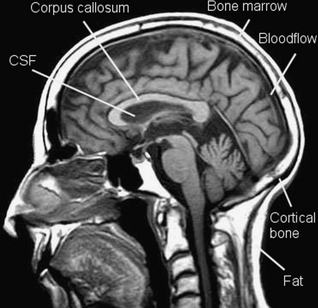

Look at Figure 39.5, a T1 weighted image. The subcutaneous fat appears bright. Cerebrospinal fluid in the lateral ventricle appears dark. White matter in the corpus callosum of the brain appears relatively bright, because it contains axons with fatty myelin sheaths. Cortical bone appears dark, because its hydrogen-1 atoms are tightly bound within a crystalline lattice and transverse relaxation between spins occurs so quickly that no signal can be sampled. But bone marrow appears bright, because it contains fat. Flowing blood in the sagittal venous sinus appears dark, because in spin echo imaging the flowing hydrogen atoms pass through an imaging slice before they can return a signal. This is known as the time of flight effect.

image

Figure 39.5 A T1 weighted sagittal spin echo image of the head and neck.